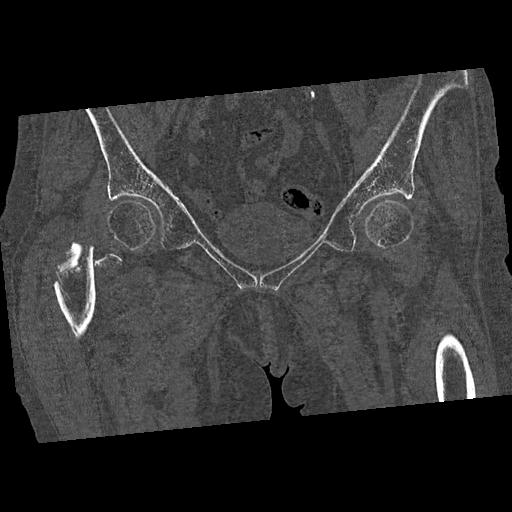

100703 1/27 両股正面+軸 1/29 両股正面+軸 94歳女性 パンソンロン